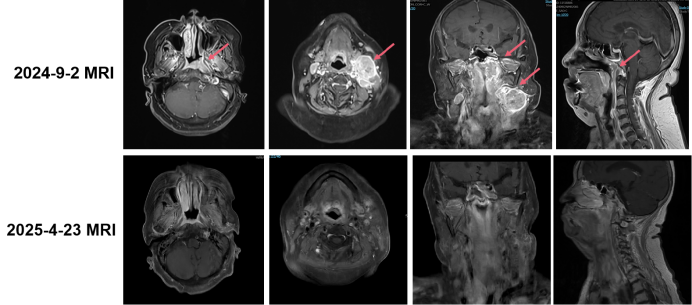

• 影像学检查(2024年11月12日 鼻咽部+颈部MR):鼻咽癌黏膜增厚较前减轻,左侧咽隐窝肿块较前缩小。双侧咽后间隙及双侧颈部多发淋巴结转移,右侧咽后间隙淋巴结较前新发,原左侧Ⅱ区较大淋巴结较前缩小,余双颈淋巴结多数较前增大。

2025423复查MRI疗效评价为CR血浆EBV-DNA为0 copies/mL

image.png

本病例展示了一例Ⅲ期鼻咽癌患者的临床治疗过程与转归。患者初始接受三周期“白蛋白紫杉醇+顺铂+特瑞普利单抗”方案治疗,后续影像学评估显示,原发灶虽有一定程度缩小,但“右侧咽后间隙淋巴结较前新发,双颈淋巴结多数较前增大(除左侧Ⅱ区较大淋巴结外)”。这提示PD-1抑制剂联合化疗方案未能有效控制疾病进展,临床需迅速调整治疗策略。

面对此不利局面,治疗团队基于对艾托组合抗体作用机制及临床应答特征的深入理解,于第四周期将治疗方案调整为艾托组合抗体联合化疗,并后续同步放疗。值得强调的是,该方案迅速展现出卓越疗效:淋巴结明显消退疗效评价达到CR,且血浆EBV-DNA持续降至0拷贝——这标志着肿瘤在影像学和分子学层面均实现了深度清除。尤为重要的是,本病例整个治疗过程中安全性表现优异,在全程使用艾托组合抗体的情况下,未出现新增的、高级别的免疫相关不良事件,这充分表明艾托组合抗体与放化疗的联合策略在临床应用中具备优异的安全性与耐受性,为全程规范治疗提供了重要保障。